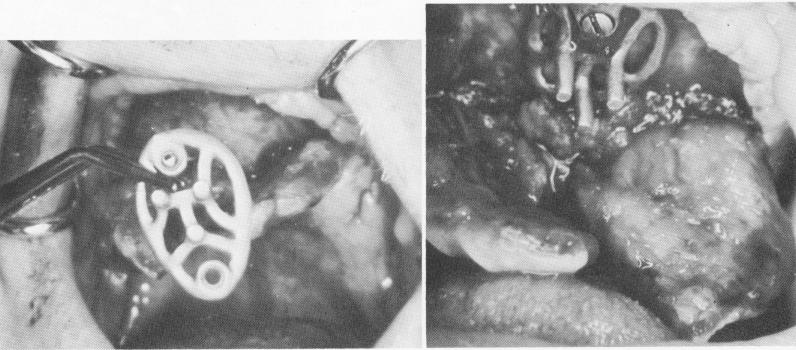

Fig. 12-113. A, The implant was fitted to the hard palate and, B, secured to it with fixation screws.